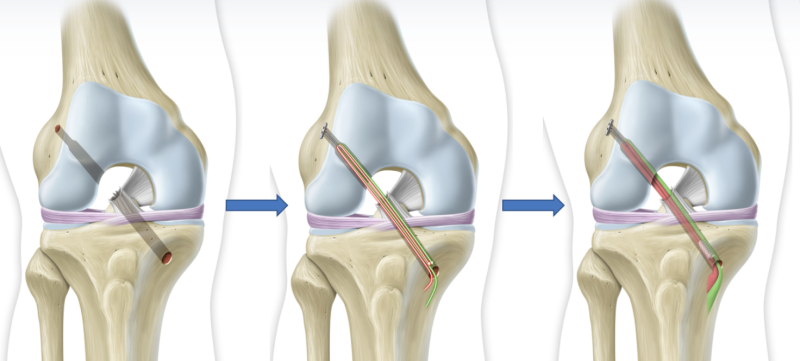

Chirurgie DIDT

L'intervention consiste à reconstruire le ligament rompu

Dr Dessyn Centre orthopédie Aubagne